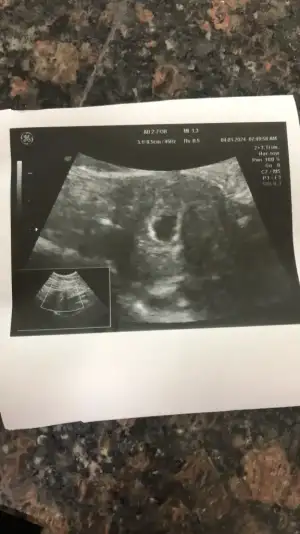

Selam canım evet 21 Aralık tı ben pazartesi günü gittim kontrole keseyi gördüm çok şükür ❤️ 2-3 hafta sonra kontrole gel dedi kalp atışı için gideceğim.. Ayy sen kalp atışını da duyarsın, o zaman gittiğinde inşallah 🐣🐣

Merhaba allah tamamına erdirsin🙏 kese görüntünüz var mı acaba